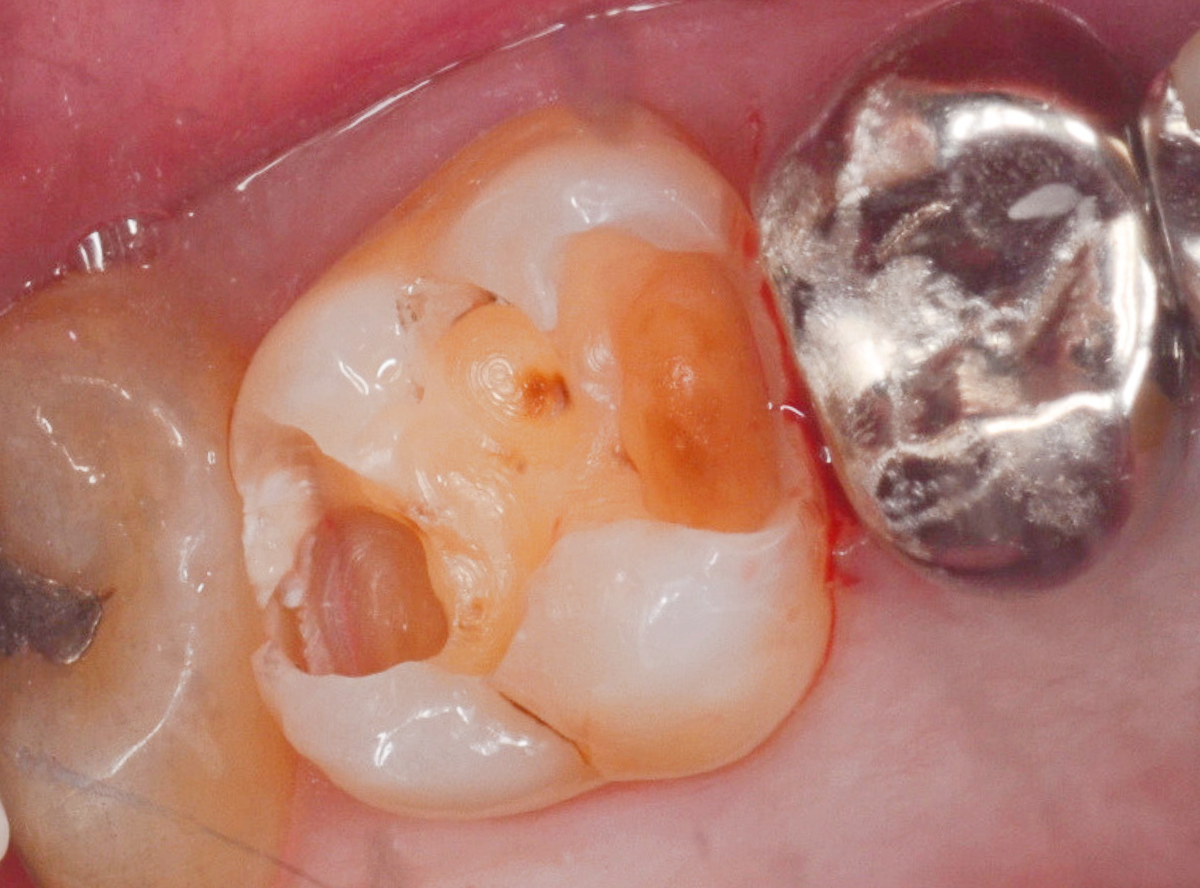

写真は、虫歯治療をしている途中の写真です。どこに虫歯があるかわかりますか?

赤く染まった部分が虫歯です。

そして、虫歯を取り切った写真を見るとかなり大きな虫歯であった事がわかります。

虫歯治療を行う上で一番大切な事は、虫歯に感染した部分をしっかり除去することですが、まずは虫歯の硬さを頼りに、軟らかくなった部分を削っていきます。

「虫歯の部分だけを削るドリル」を使用すれば、それだけでほぼ虫歯は取り除けますが、感染部位を完全に除去できたかわかりづらい時もあります。

このう蝕検知液を併用することで、虫歯を取り残すことなく虫歯治療ができます。

う蝕検知液で細かくチェックする事で、虫歯治療の精度があがります。